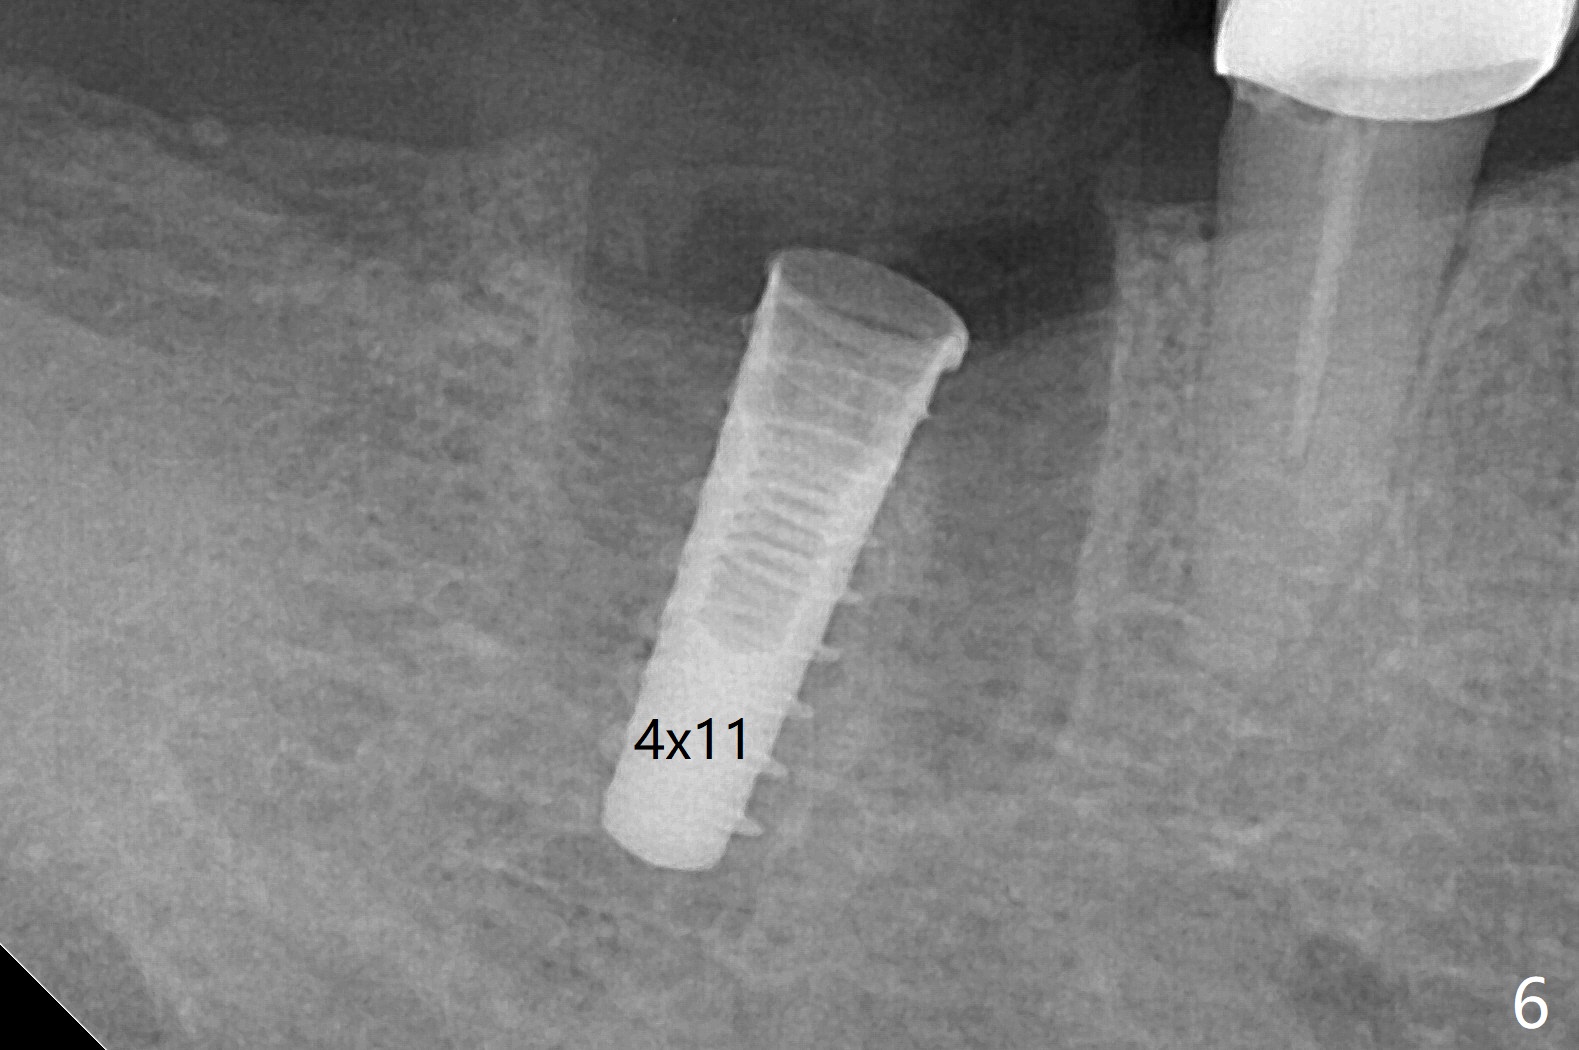

A 59-year-old woman with severe pain and mobility at #30 returns to clinic for extraction and implant on emergency basis (Fig.1 ^: crazing line). To prevent osteotomy deviation off the septum, the crown is sectioned (Fig.2) and the coronal end of the septum is exposed. In fact the initial osteotomy is blind (Fig.3). After increasing the access (Fig.4), trying to change trajectory and increasing the depth and diameter of the osteotomy, the trajectory deviates to the distal socket (Fig.5). Following root extraction, debridement of the sockets and minor trajectory change, a 4x11 mm dummy implant is placed (Fig.6). With a drastic change in osteotomy, the dummy implant position is somewhat acceptable with a 5.2x4 mm planning abutment (Fig.7 P). After placement of bone graft around the 4.5x11 mm final implant to enhance stability, a 5.5x4(3) mm definitive abutment is placed in a restorable position (Fig.8). The implant turns while the abutment screw is hand tightened. Since there is an apical space (Fig.8 <), the implant is then placed ~ 1mm deeper with ~ 30 Ncm (Fig.9). A longer cuffed abutment is inserted and more bone graft is placed (*). In summary, roots in the sockets do not seem to help free hand osteotomy in the lower 1st molar. It is also difficult to control pain during acute infection. Block anesthesia has to be administered, increasing the chance of nerve injury. Either guided surgery or delayed implant should be conducted. There is no postop paresthesia, although the buccal gingiva is slightly erythematou, edematous and tender 1 week posotp. Oral Amoxicillin is prescribed for one more week. The keratinized gingiva (Fig.10 ^) and the papilla (*) are maintained in place around the immediate provisional (P) 2 months 20 days postop. The soft tissue remains normal 4 months postop (Fig.11) and immediate pre cementation (Fig.12).